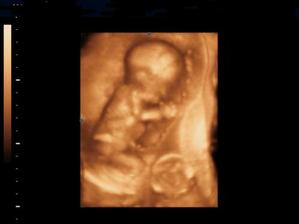

Naše kinderka

Dňa 24.8.2009 o 9.15 sa nám sekciou narodili naše krásne dvojičky Vanesska 2280 g a Larinka 2990 g. Robia nám veľkú radosť a moc ich ľúbime...